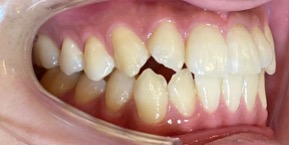

34歳女性のビフォーアフター

| 診断 | 叢生(デコボコがある状態)、開咬、下顎前突 |

| 治療方針 | インビザラインシステムにて主にIPR(歯と歯の間をわずかに削合してスペースを獲得する方法)を組み込んだ動的矯正治療を行った叢生改善と、開咬の改善のため臼歯部圧下をメインとした動的治療を行い、保定を行う。 |

| 治療費 ※ | 99万7千円(診断、型取り、PMTC、保定装置を含む料金) |

| 治療期間 | 3年5か月 |

| リスク | 1日20時間以上マウスピースを使用できない場合、歯が動かない可能性がある。装着時や食事時に痛みを伴う。歯肉退縮や虫歯になるおそれがある。また、指導通りに装着できていない場合や適切なブラッシングが出来ていないとそのリスクが高くなる。歯根が短くなることがある。ごくまれに歯の神経が損傷してしまうことがある。過去にぶつけたり深い虫歯治療をしたことがあるとそのリスクはやや高くなる。矯正後には保定装置が必要。適切な使用ができない場合、後戻りの原因となる。将来的に歯並びが動いて再矯正が必要な場合がある。舌癖が強い場合や正常に生えていない親知らずがある場合、その可能性が高くなる。 |

※ 治療費は、治療当時の費用で、現在の費用と異なる可能性があります。現在の費用は治療費のページでご確認くださいませ。